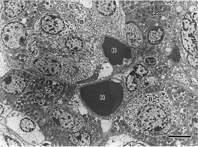

写真−2 電子顕微鏡像(bar=500μm)

チモーゲン顆粒を有する外分泌細胞(暗調

な細胞質)と共に顆粒を有する内分泌細胞

(明調な細胞質)が混在して見られる。

Z:チモーゲン顆粒

B:β顆粒

H:血管